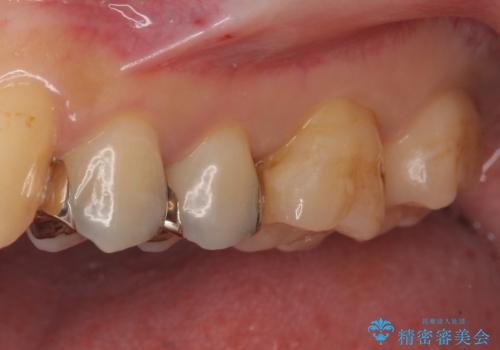

- 銀の詰め物を白くしたいとのことで来院。

銀の詰め物を除去した後、う蝕が残っていないかを拡大鏡下で確認し

セラミックの詰め物(e-maxインレー)にて治療を行いました。

メタルインレーをそのままにしておくと、歯と詰め物の隙間から細菌が入り込み

虫歯の再発リスクが高まります。